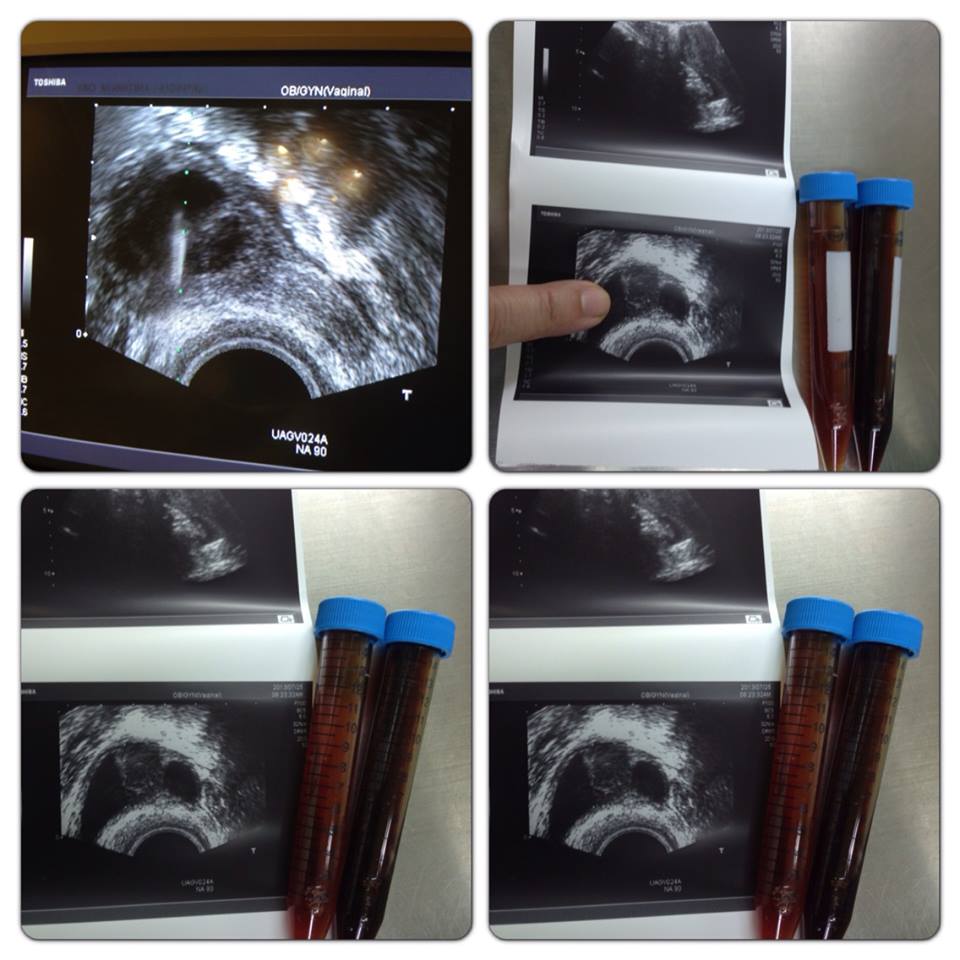

香港HongKong來彰化博元婦產科做試管嬰兒!她有巧克力囊腫,博元免費幫她完全吸乾淨!